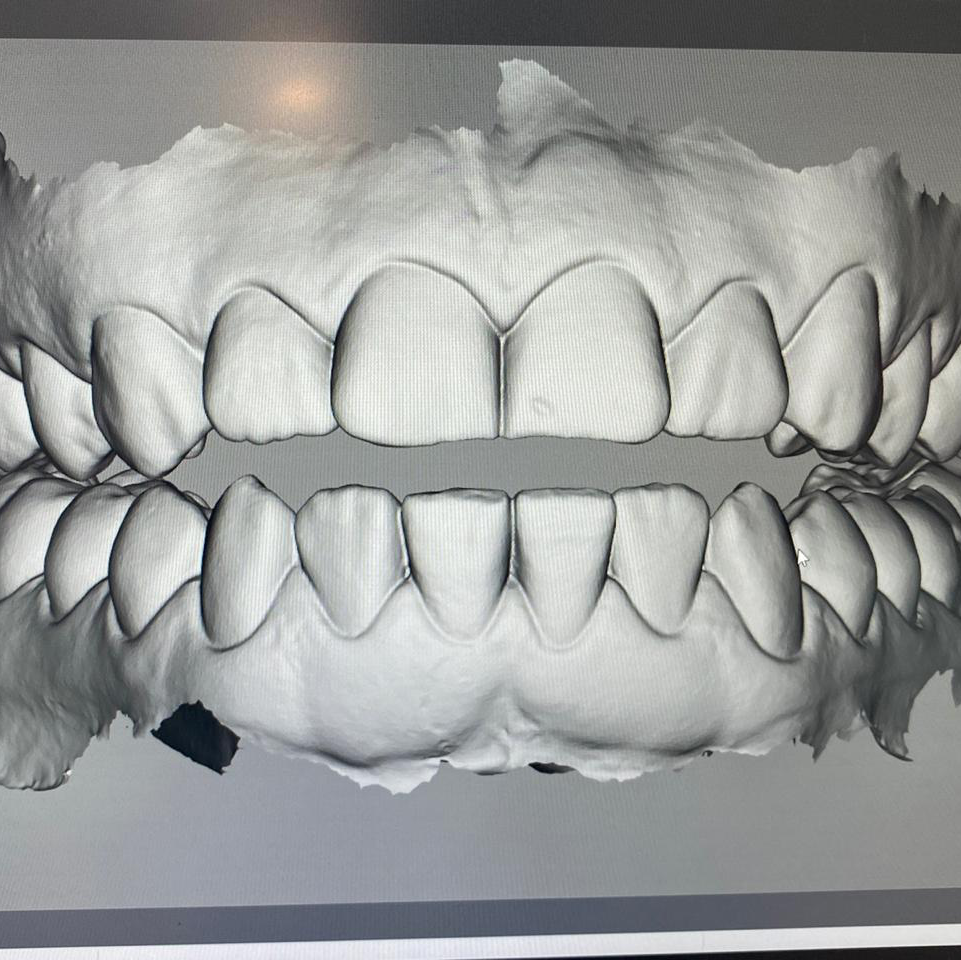

Dr. Ricardo Velázquez García es un dentista destacado en Colima, especializado en implantes dentales y cuidado integral de la salud bucal. Ubicado en el Centro Médico Puerta de Hierro, en Calle Ignacio Sandoval 1699-Consultorio 312, Girasoles, ofrece un ambiente profesional y acogedor para todos sus pacientes. Con una sólida reputación respaldada por una calificación de 5 estrellas basada en 235 opiniones, el Dr. Velázquez se distingue por su atención personalizada y la calidad de sus tratamientos. Sus pacientes valoran especialmente la amabilidad del equipo, la limpieza profunda y los resultados efectivos, como blanqueamientos dentales y procedimientos de bonding. La clínica cuenta con tecnología avanzada y un equipo comprometido en brindar una experiencia cómoda y segura. Para agendar una cita o solicitar información, puede comunicarse al teléfono 312 688 2357 o visitar su sitio web oficial https://dentaldesign.acecli.cloud/. El Dr. Ricardo Velázquez García es una opción confiable para quienes buscan mejorar su sonrisa y mantener una salud dental óptima en Colima.

Dr. Ricardo Velazquez García is a highly regarded dentist in Colima, specializing in dental implants and comprehensive oral health care. Located at Centro Medico Puerta de Hierro, Calle Ignacio Sandoval 1699-Consultorio 312, Girasoles, the clinic provides a professional and welcoming environment for all patients. With a 5-star Google rating from 235 reviews, Dr. Velazquez is known for his personalized approach and high-quality dental treatments. Patients appreciate the friendly and professional staff, thorough cleanings, and effective results including teeth whitening and bonding procedures. The clinic is equipped with advanced technology and a team dedicated to delivering a comfortable and safe experience. To schedule an appointment or request more information, contact the office at 312 688 2357 or visit the official website at https://dentaldesign.acecli.cloud/. Dr. Ricardo Velazquez García is a trusted choice for those seeking to improve their smile and maintain excellent dental health in Colima.